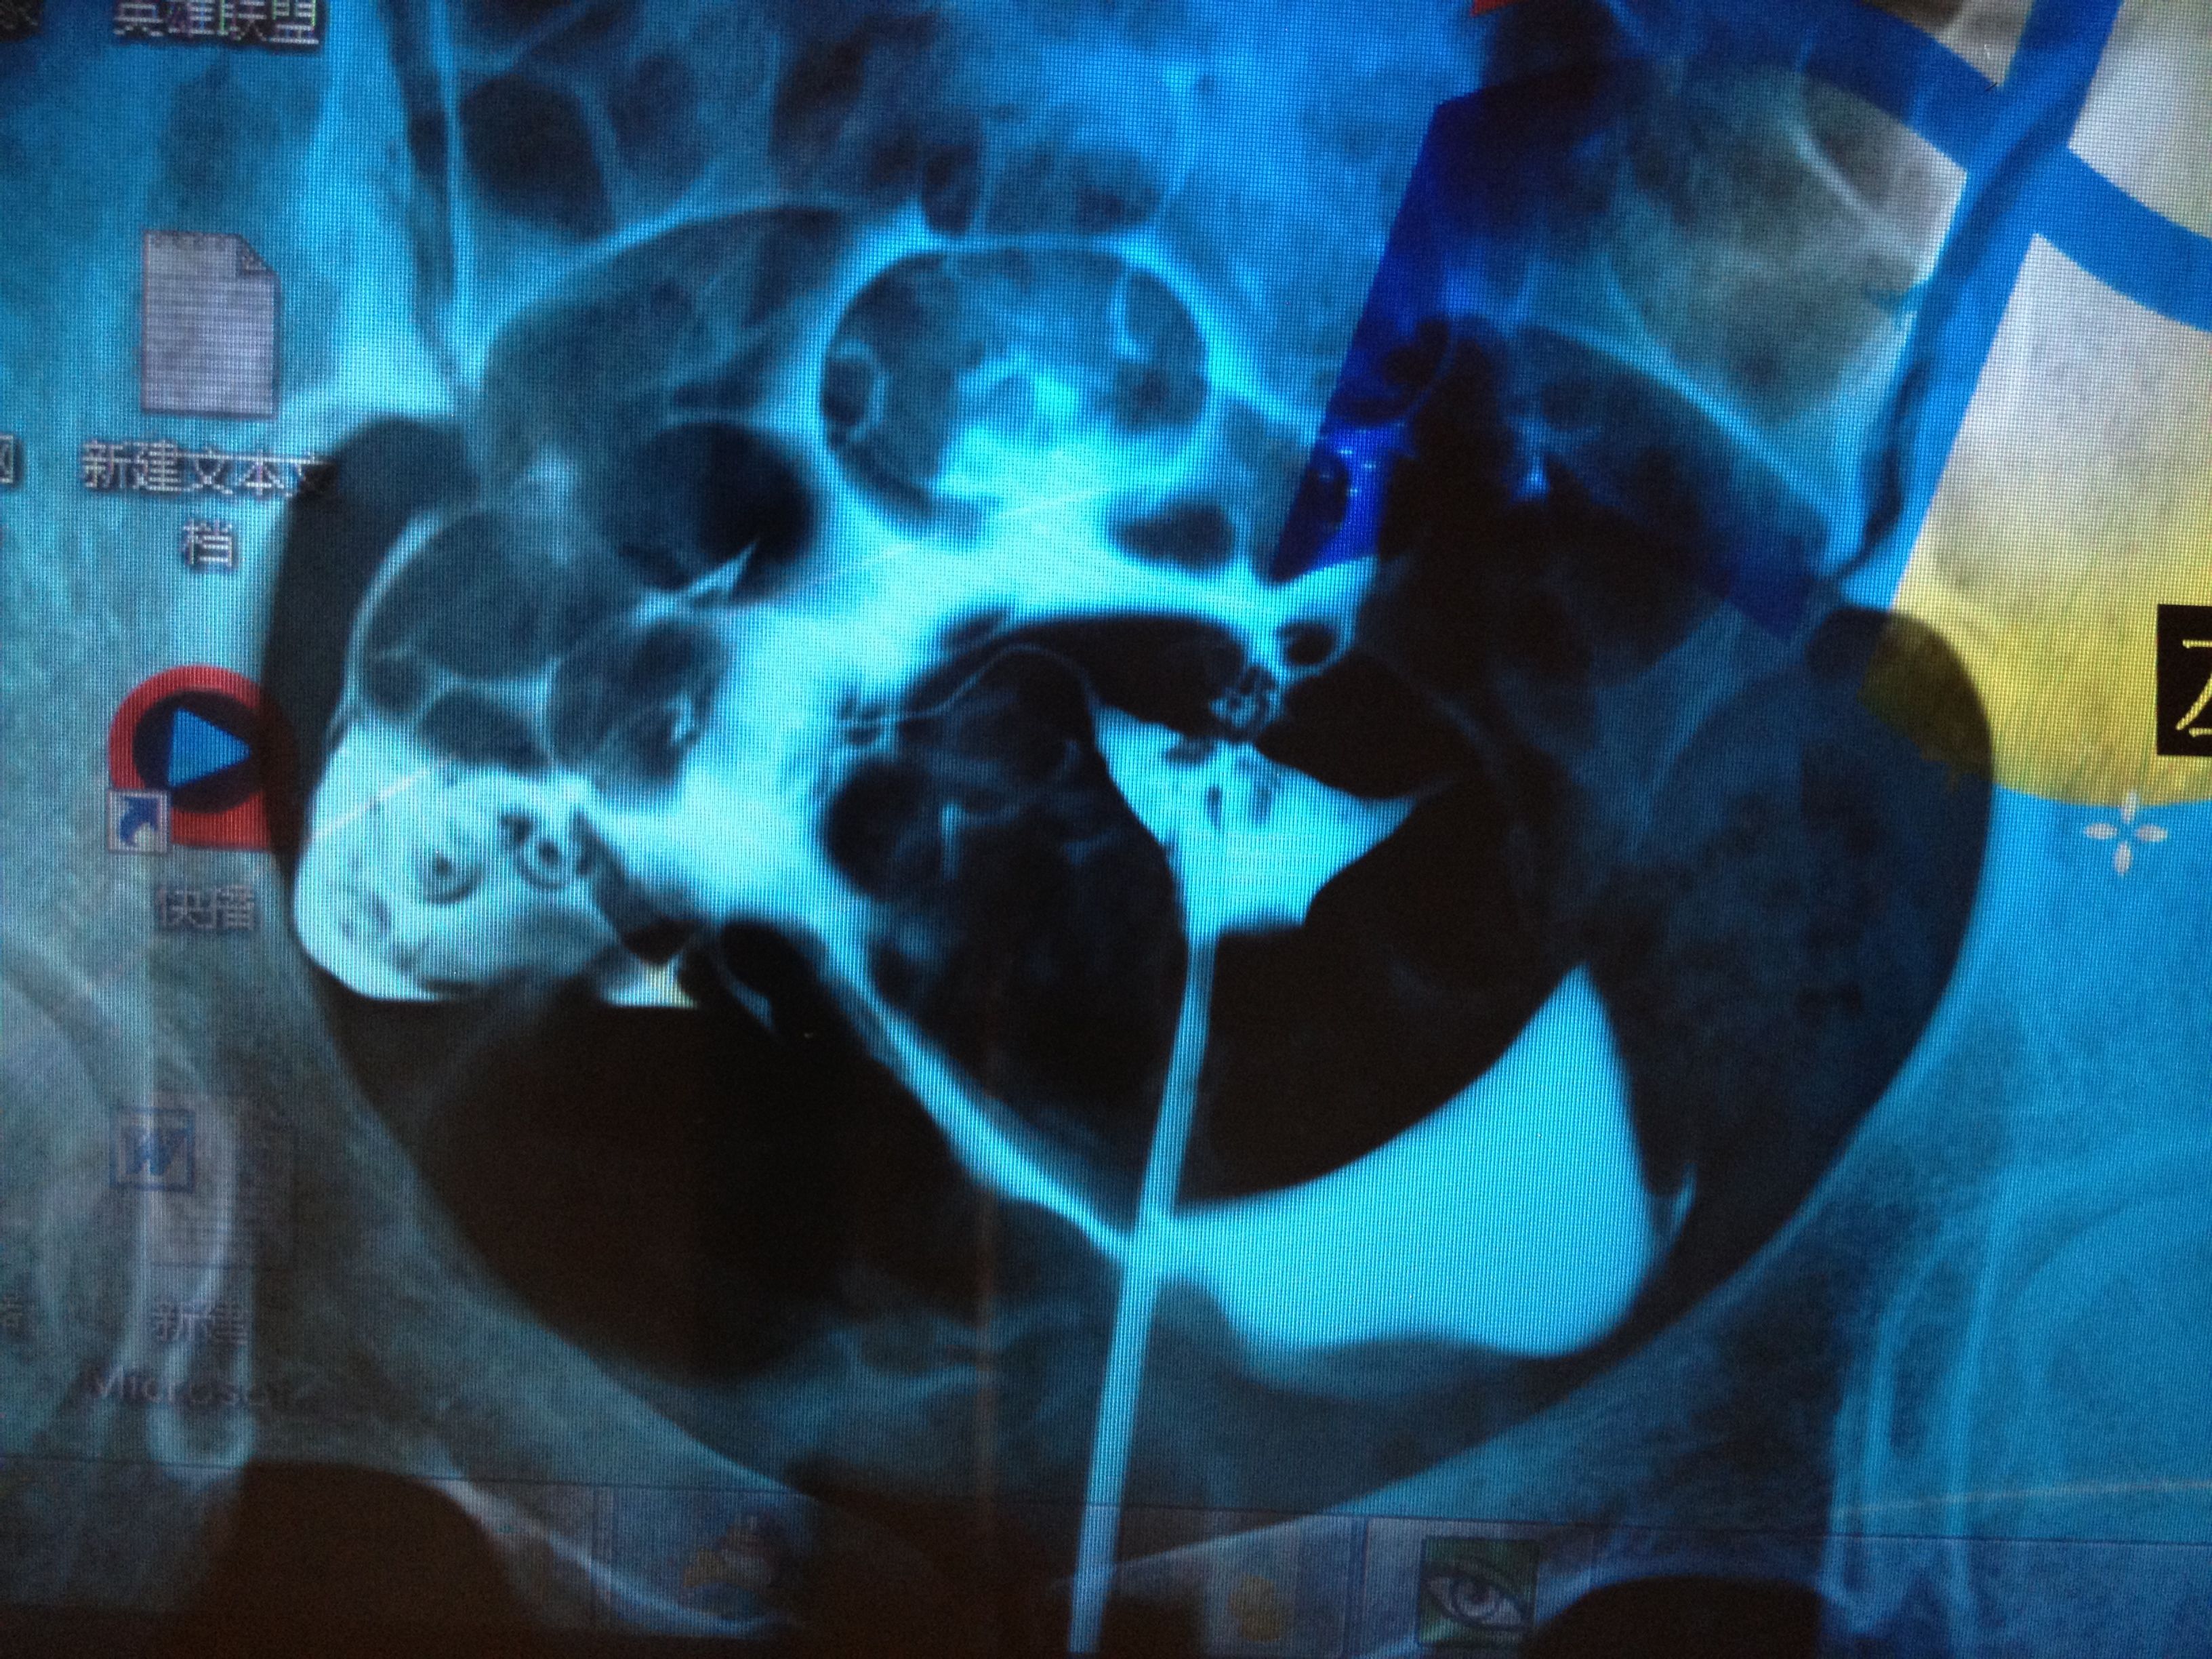

前面的影像是正常的,我就从左右侧描述说吧,两侧宫角充盈完整,右侧输卵管自宫旁连续显影,走行自然,光

滑,并见部分照影剂自该侧伞端溢入盆腔,并见少许弥散。左侧输卵管大致 显影至壶腹区附近,进一步注入照影剂未见任何进展。第三张片于盆腔内可见散在片絮状及条弧状照影剂影,弥散尚可以。医生说右侧细,可能有炎症,左侧不通,两侧都得通水,我想问问有通水的必要吗?还有我的右侧是不是良好的?还是有炎症,还有偏细?应该怎么治疗?前两张是刚开始的,后两张是20分钟后的。还有现在拿到抗精子化验单有一项是阳性?怎么办?还有那个准吗?